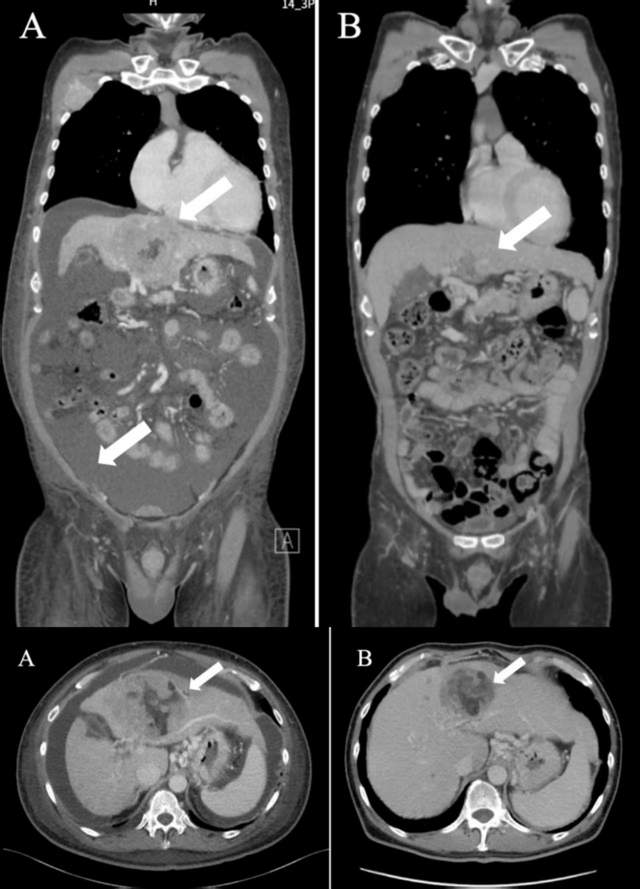

一位30多岁的女性患者,确诊时已是IV期子宫内膜癌,伴有腹膜、肝、肺、骨多处转移和大量腹水。在常规化疗效果有限的情况下,她接受了WT1-DC疫苗、高活性NK细胞联合免疫检查点抑制剂(纳武利尤单抗)的治疗。经过几个疗程,影像学复查显示,其肺转移灶和腹膜播散灶完全消失,肝转移灶显著缩小,腹水明显减少。

这位61岁晚期肝细胞癌男性患者,伴有多发淋巴结转移、多肺转移和骨转移。采用靶向WT1及α-半乳糖神经酰胺的DC疫苗,联合NK细胞及纳武利尤单抗的三联方案后,患者肿瘤缩小,腹水消失。